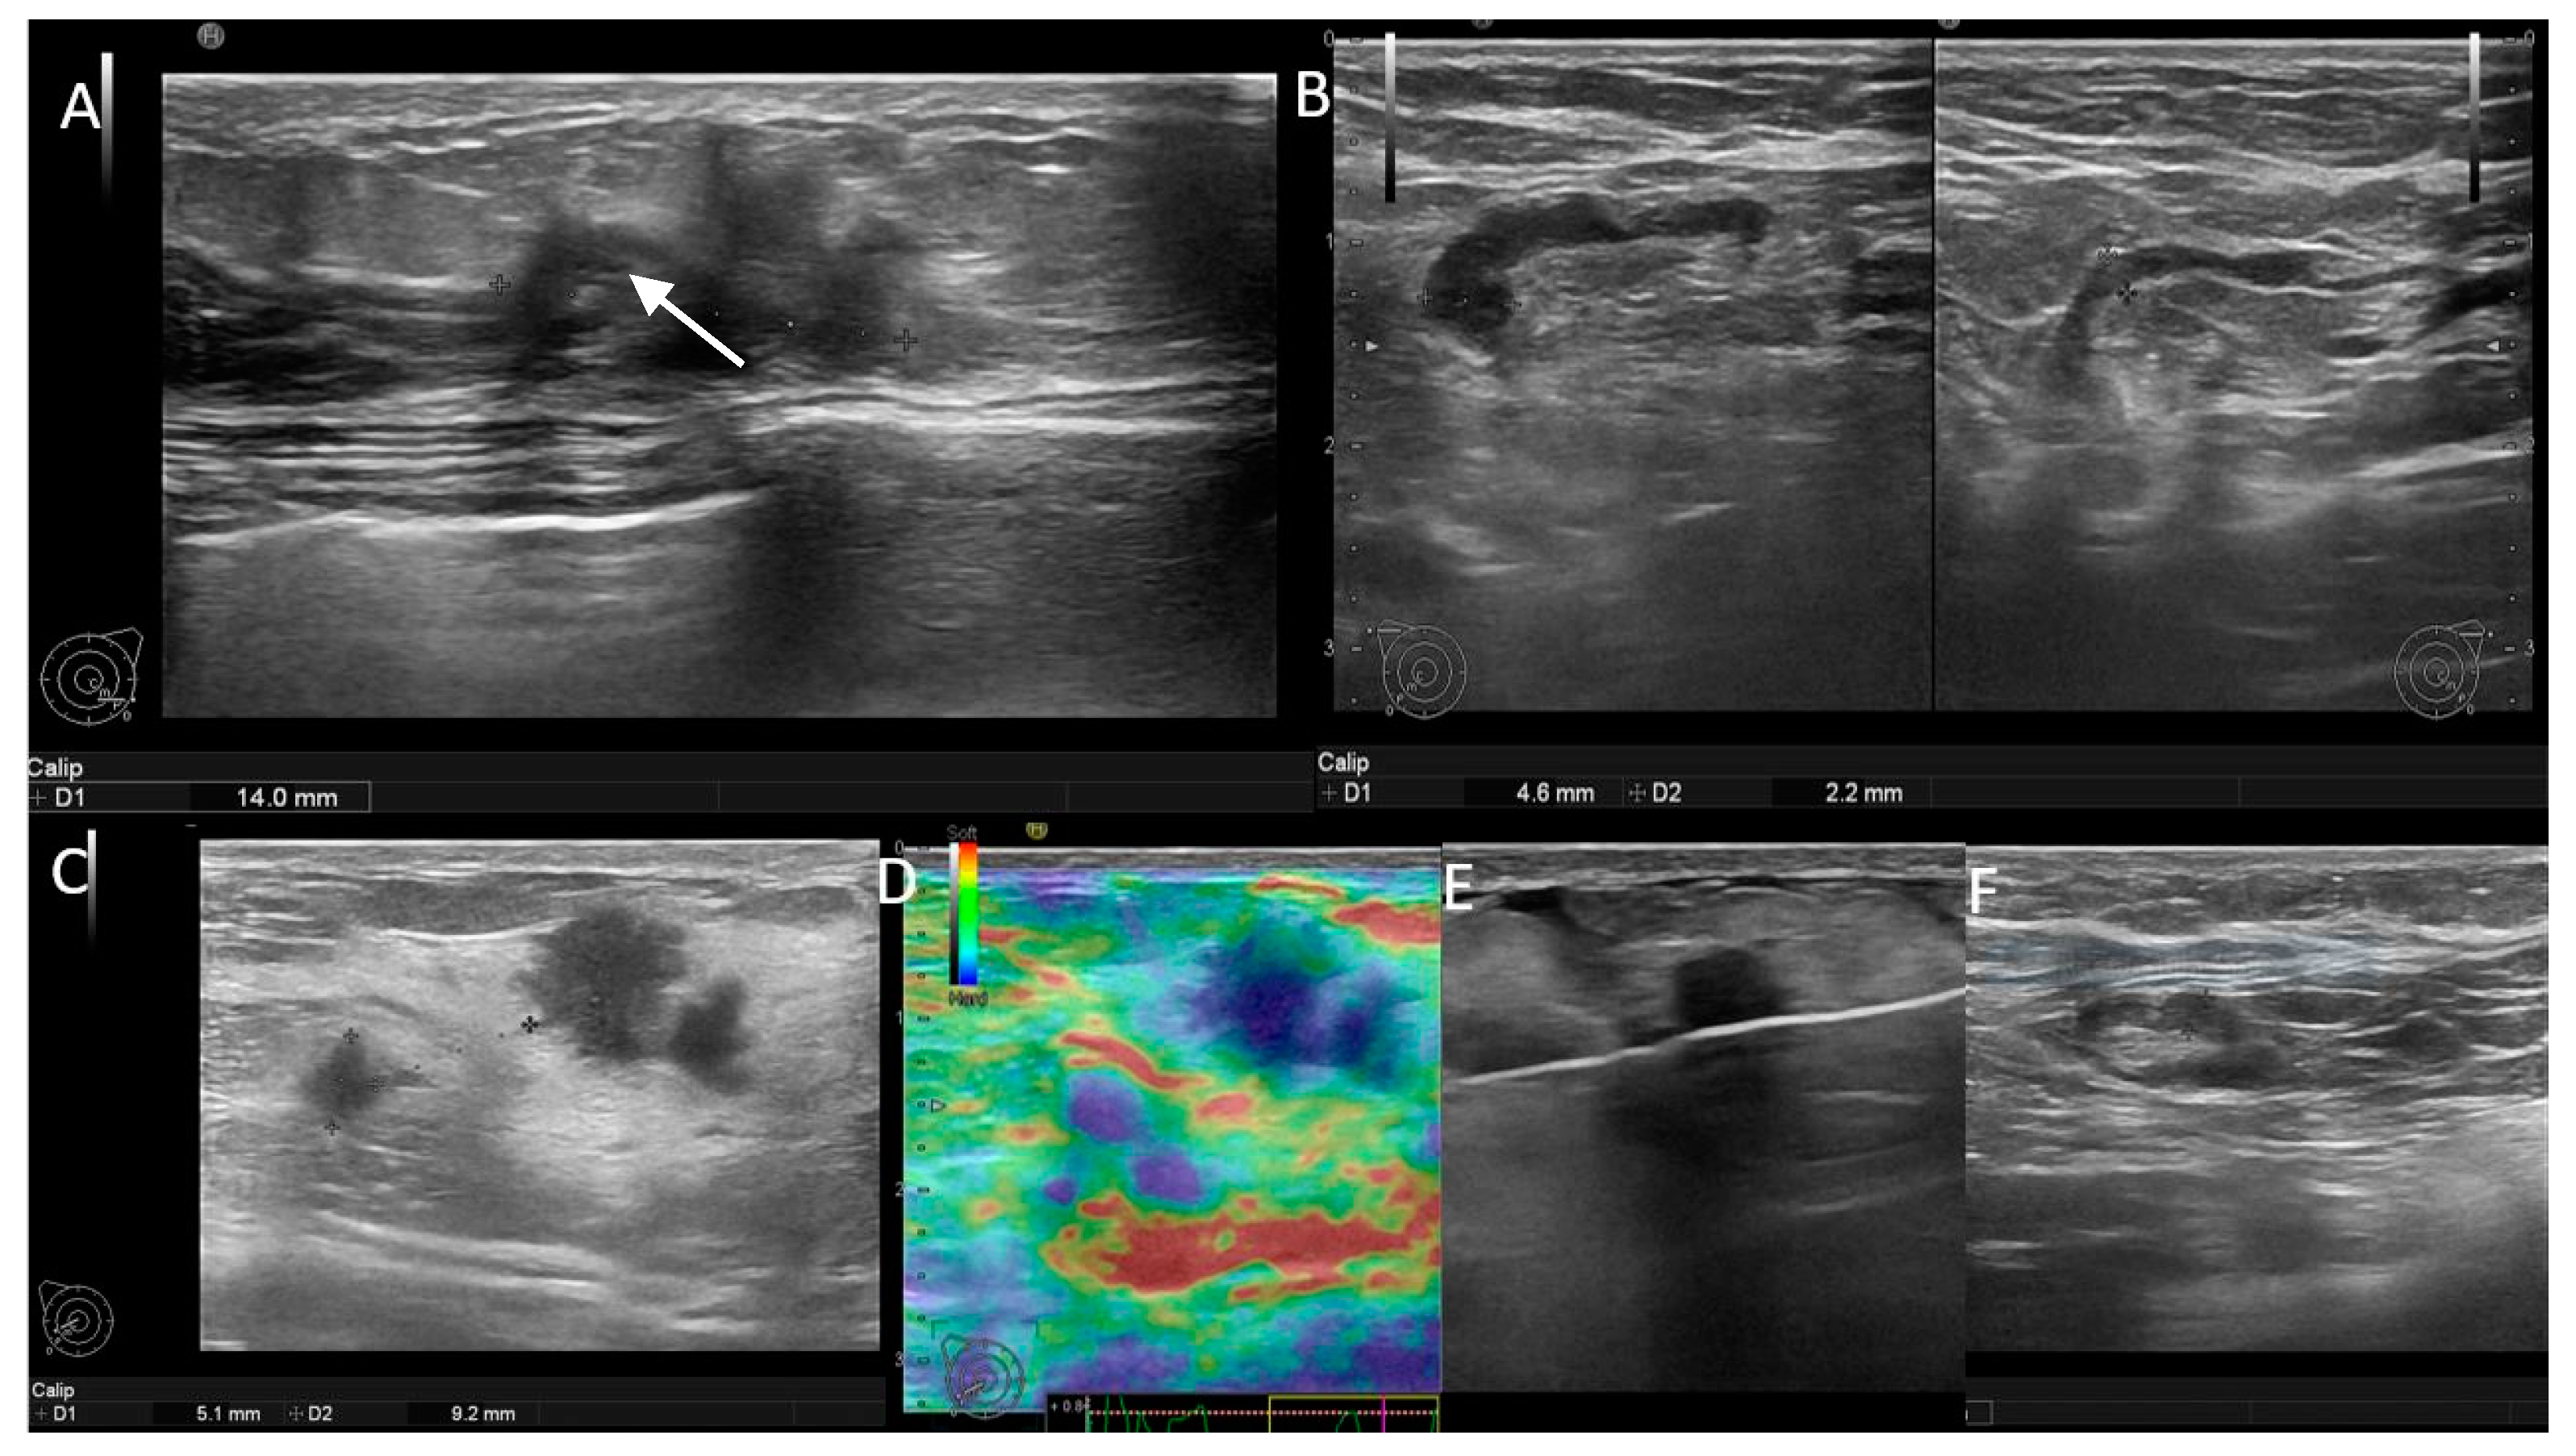

Figure 2. (A,B) Patient with negative genetic testin-unifocal BIRADS 5 mass and positive axillary US. There is an ipsilateral lymph node with cortical thickness up to 4.4 mm (white arrow), compared to the contralateral node, which has only 2.2 cortical thickness. (CF) Patient with BRCA2 mutation-bifocal BIRADS 5 masses and negative axillary US. There is an ipsilateral node with fatty hilum and a thin cortex of 2 mm.